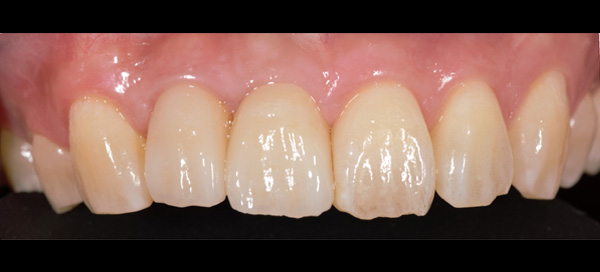

AFTER

| 年代・性別 | 30代 女性 |

|---|---|

| 主訴 | 左上の乳歯がグラグラしてきた |

| 治療期間 | 約12ヶ月 |

| 費用 | 550,000円 |

| 治療内容 | インプラント、骨造成、セラミック修復 |

| 治療に伴うリスク | インプラント周囲炎 セラミックの破折、脱離 |